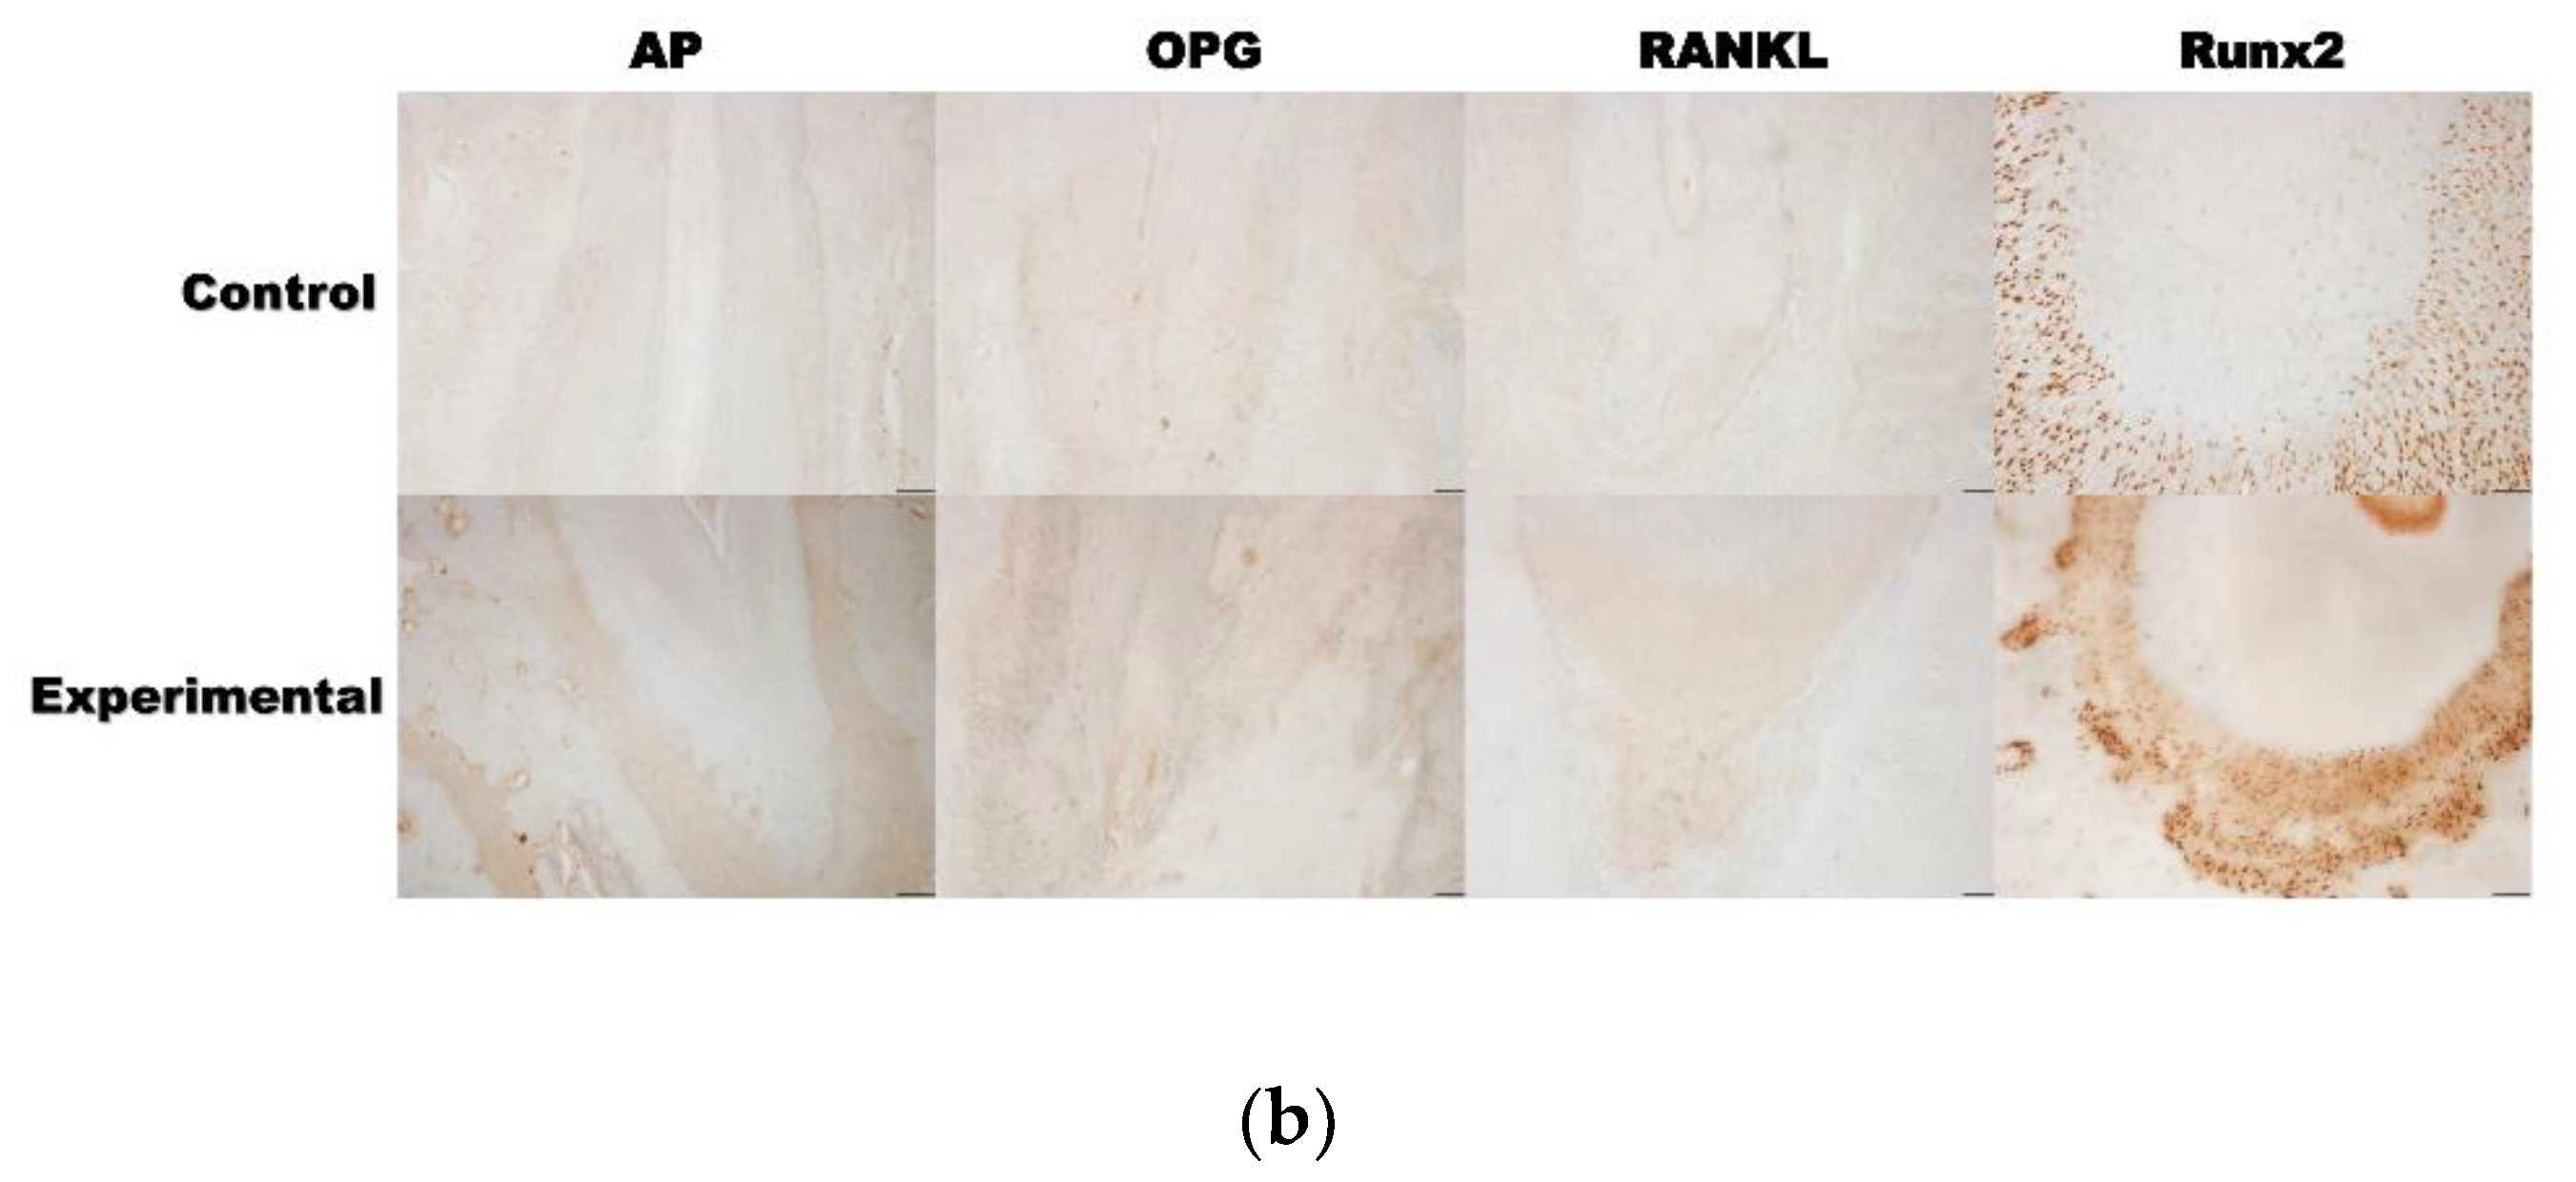

3.2. 4HR Increased OPG, RANKL, AP, and Runx2 Expression in Tissue